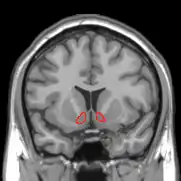

Figure 2. The sensation of tickle is perceived by the part of the brain called the somatosensory cortex.

Research studies using functional magnetic resonance imaging (or fMRI) have found the increased activity of certain brain parts when one experiences the sensation of tickle. An increased cerebral blood flow in the somatosensory cortex - or S1 - is shown in response to tickle induced by an external stimulus (McGlone et al., 2002). This particular area of the cortex is the primary receiver of sensory inputs from the body relayed via the thalamus (Hine & Martin, 2015). The S1 occupies the postcentral gyrus and is devoted to process information from the somatic receptors (Colman, 2008). When one receives an externally administered tactile stimulus that produces the tickle sensation, the S1 shows an increased activity, suggesting that tickle is indeed a fundamental sensation of the skin.

One of the unique characteristics of tickling is that one cannot make oneself laugh via self-tickling. The sensation of tickle is perceived by a part of the brain called the somatosensory cortex, or S1. However, when tickle is felt as a sensation resulting from a self-produced stimulation, the S1 does not show the same increase in activity as it does during an externally administered stimulation (Blakemore, Wolpert, & Firth, 1998). This suggests that a self-produced tactile stimulus is perceived by the brain as less ticklish than the same stimulus generated externally. It is important to note, however, that most research on the subject relies heavily on self-report, and subjective experiences of the sensation of tickle vary among individuals (Simpson, 2001). Thus, further research using a different method is required to reduce the current strong degree of subjectivity.